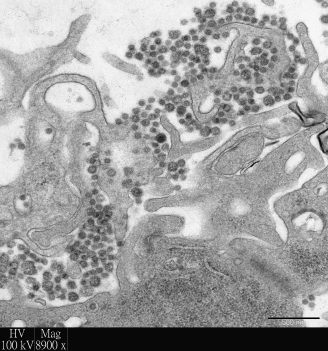

Researchers at the Li Ka Shing Faculty of Medicine of The University of Hong Kong (HKU) used their world-leading human respiratory explant culture system to investigate emerging respiratory viral infections, and in their latest publication focused their attention to improve the treatment of the deadly Middle East Respiratory Virus Syndrome (MERS). It is demonstrated that a combination of two currently licensed agents – interferon and cyclosporine, was able to significantly inhibit virus replication and tissue damage by the MERS coronavirus in human bronchus and lung, when compared to single agent treatment or no treatment. Their findings are now published in Anti-Viral Research, the leading journal of anti-viral treatment (link to the publication).

The explant culture system of the human respiratory tract was developed by Professor John Nicholls of HKU Department of Pathology, in conjunction with Dr Michael Chan, Dr Renee Chan, Professor Leo Poon and Professor Malik Peiris at the School of Public Health, in 2005, in order to develop a laboratory based method for studying severe respiratory virus infections with a more faithful replication of disease mechanisms and treatment outcomes in humans. The system is proved to be more effective for the study than alternative experimental methods, such as cell lines grown in culture or experimental animals, as the latter often fail to reproduce the situation in human respiratory tract.